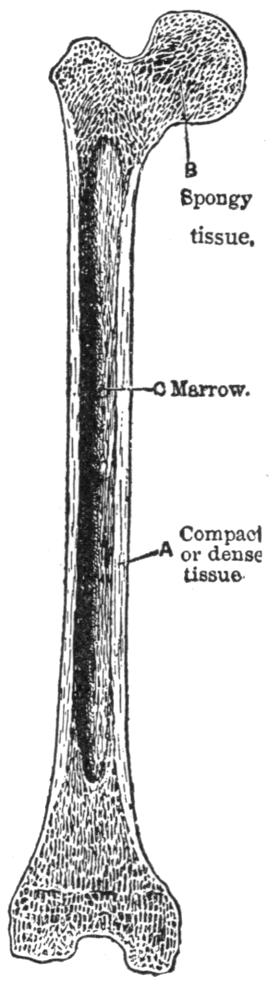

| III. | The Skeleton | H 28 |